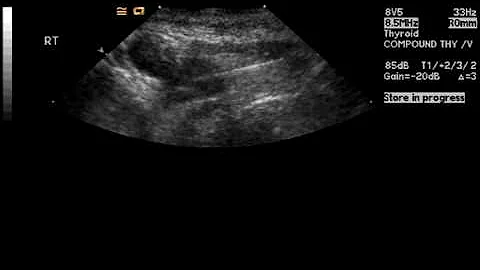

Ultrasound Guided Needle Biopsy Techniques Video 4 - Sampling Techniques Fna

IMV imaging's in-house vet Ben Sullivan BVSc MRCVS presents a new video series "Ultrasound Guided Needle Biopsy ...